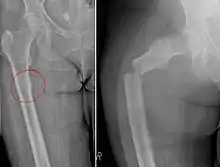

Chalkstick fracture due to bone metastasis of breast cancer. Left image shows the metastasis, on the right a pathological fracture a few days later.

Chalkstick fractures are fractures, typically of long bones, in which the fracture is transverse to the long axis of the bone, like a broken stick of chalk.[1] A healthy long bone typically breaks like a hard woody stick as the collagen in the matrix adds remarkable flexibility to the mineral and the energy can run up and down the growth rings of bone. The bones of children will even follow a greenstick fracture pattern.